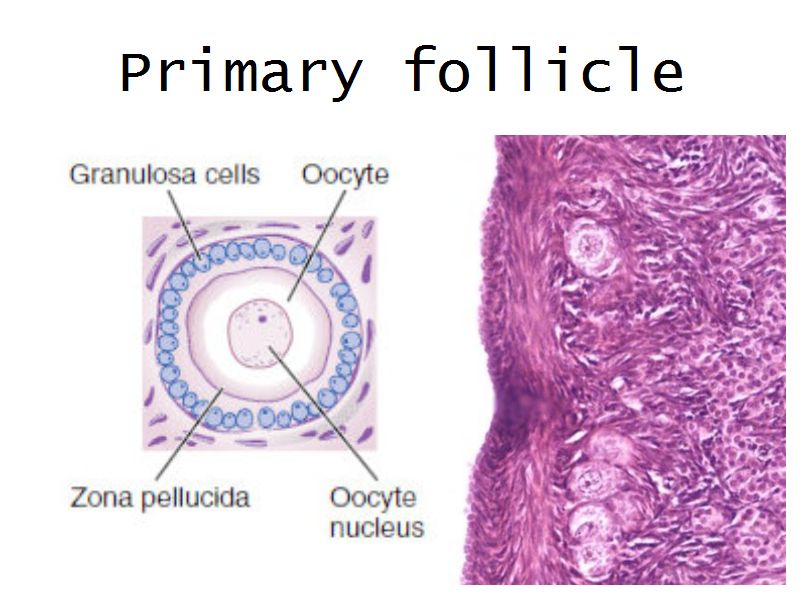

Follicular maturation

- Primordial follicle

- Growing follicle

- Primary follicle

- Secondary follicle

- Mature follicle (Graafian)

Components of a follicle

- Theca

- externa

- interna

- basal lamina

- Granulosa cells

- Antrum

- Cumulus oophorus >> Corona radiata

- Oocyte